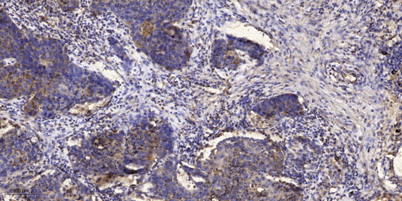

| Dilutions: | WB 1:500-2000;IHC-p 1:50-300 |